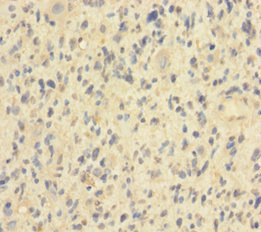

• Immunohistochemistry of paraffin-embedded human glioma using CSB-PA857877LA01HU at dilution of 1:100

• IHC image of CSB-PA857877LA01HU diluted at 1:600 and staining in paraffin-embedded human brain tissue performed on a Leica BondTM system. After dewaxing and hydration, antigen retrieval was mediated by high pressure in a citrate buffer (pH 6.0). Section was blocked with 10% normal goat serum 30min at RT. Then primary antibody (1% BSA) was incubated at 4°C overnight. The primary is detected by a biotinylated secondary antibody and visualized using an HRP conjugated SP system.